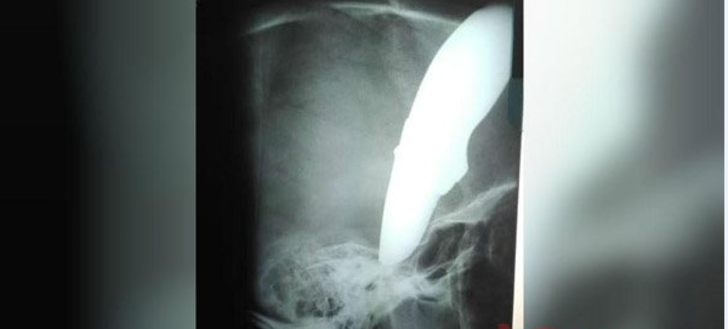

34 yaşındaki Shaun Wayne'i görenler hayretler içinde kaldı. Wayne'in kafatasına saplanmış 15 santimetrelik bir bıçak vardı.

Bisikletçinin annesine kafatasının tamamen iyileşeceğini söyleyen Dr. Brendan Venter, Wayne'nin çok şanslı olduğunu belirtti.

Yerel medya, 34 yaşındaki erkeğin bisikletini gasp etmek isteyen saldırganların bıçak kullandığını bildiriyor.